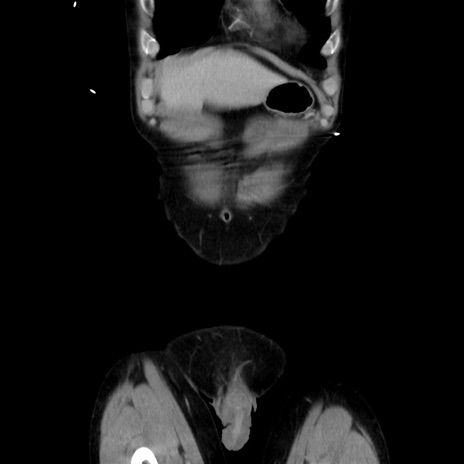

症例37(冠状断像)

【症例】40歳代 男性

【主訴】腹痛

【現病歴】4時間ほど前に電車に乗車中に臍部上より腹痛出現。徐々に増悪し起立困難となり、救急外来受診。生ものは数日食べていない。今朝お雑煮を食べた。

【身体所見】BT 36.8℃、BP 117/84mmHg、HR 91/min、SpO2 97%、苦悶様、腹部:臍上部広範囲圧痛あり、反跳痛±

【データ】WBC 8100、CRP 0.03